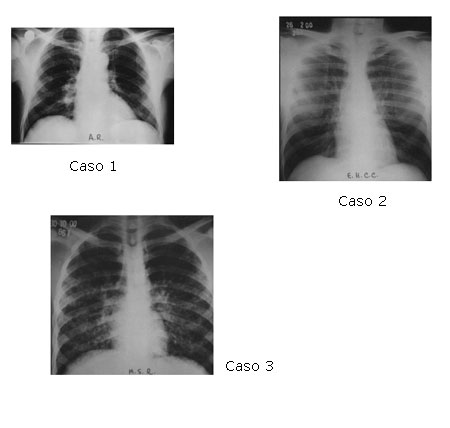

Os principais dados clínicos e laboratoriais dos três pacientes são apresentados na tabela 1; a figura 3 mostra as radiografias de tórax.

Figura 3 – Radiografias de tórax dos três pacientes com Aids e histoplasmose disseminada, mostrando infiltrados pulmonares de padrões variados e inespecíficos.

Na prática, o diagnóstico de histoplasmose disseminada é mais freqüentemente pensado diante de pacientes com Aids e febre, hepato e/ou esplenomegalia e pancitopenia. Entretanto, diferentes estudos mostram que a hepatoesplenomegalia pode ocorrer em aproximadamente 70% dos pacientes [8], ou em apenas 25% deles [4]. A linfonodomegalia é observada em 25 a 50% dos casos, enquanto mais de 40% dos pacientes podem ter lesões cutâneas [7,8]. A anemia é um achado comum no hemograma, podendo ser acompanhada de leucopenia e/ou plaquetopenia; a pancitopenia, entretanto, é descrita em cerca de apenas um terço dos casos [8]. As alterações radiológicas pulmonares da histoplasmose são inespecíficas e 30% dos pacientes podem ter Rx de tórax normal[2].

Os três pacientes apresentavam emagrecimento, febre e diarréia, além de infiltrado pulmonar, manifestações que são comuns a outras doenças acometendo pacientes com Aids. Em nosso meio, como a infecção por Mycobacterium tuberculosis é freqüente, muitos pacientes com histoplasmose recebem tratamento empírico para tuberculose enquanto aguardam esclarecimento diagnóstico, como no caso 2. Este esclarecimento, entretanto, nem sempre é feito ou ocorre tardiamente. É certo que muitos pacientes demoram a procurar serviço médico ou, se procuram, o diagnóstico da micose não é pensado ou, sobretudo, a disponibilidade de exames para a sua realização é restrita. Nos três pacientes apresentados, o intervalo entre o início dos sintomas e a internação variou de 20 a 100 dias. O curso da doença foi fatal nos três casos, que evoluíram com insuficiência renal, acidose metabólica não responsiva às medidas habituais e óbito 3 a 21 dias após a internação.